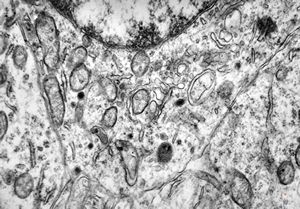

F,25y. | myopathy - atrophic and regenerating muscle cells